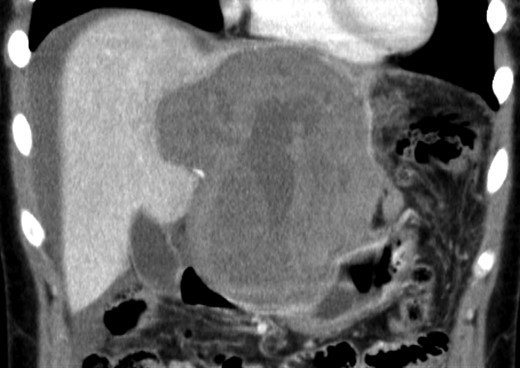

An 18-year-old woman presented with epigastric pain that started during a Japanese drum lesson. She was diagnosed with rupture of a hepatic tumor and transported to our hospital. She had no medical history of surgery, including abdominal surgery. Contrast-enhanced computed tomography (CT) revealed a 13-cm, low-density giant mass in the left hepatic lobe and high-density ascites, indicating abdominal bleeding from the liver tumor (Fig. 1). Ultrasonography confirmed a well-defined giant mass of the liver, comprising both cystic and solid lesions. Laboratory data showed a low hemoglobin level of 8.2 g/dl, and all the results of liver function tests and tumor marker measurement were within normal ranges. The patient underwent emergent celiac angiography, which revealed an avascular tumor with no evidence of extravasation from the hepatic artery. The left hepatic artery was considered to be the artery feeding the tumor and was embolized (Fig. 2). Magnetic resonance imaging (MRI) confirmed a well-defined giant multilocular lesion with fibrous partition (Fig. 3). After the patient's condition stabilized, she underwent left hepatic lobectomy. Laparotomy revealed bloody ascites and a large tumor in the left lobe of the liver; the right lobe appeared normal. The enlarged lymph nodes of the hepatoduodenal ligament were also dissected. Histological analysis of the resected specimen revealed a huge cystic mass of ∼12 × 9.5 cm. The mass was cystic and multilocular with a fibrous wall and filled with a massive blood clot (Fig. 4). The enlarged lymph node had a 25 × 23-mm cyst, which contained yellowish fluid. On microscopic examination, the wall of the cyst consisted of a tight elastic fiber meshwork composed of collagen fibers, which was accompanied by a small amount of acid mucopolysaccharide in the stroma and a lining of single-layered flat cells on the inner wall (Fig. 5a and b). Immunohistochemical staining revealed that the cyst wall was positive for both the endothelial marker CD31 and the lymphangial marker D2-40 (Fig. 5c and d). The cystic structure of the lymph node also was composed of elastic fiber components similar to those of the cyst in the liver and lined with single-layered flat cells, which were immunohistochemically positive both for CD31 and D2-40 (Fig. 5e). The pathological diagnosis was hepatic lymphangioma combined with lymphangioma of the lymph nodes. The patient's postoperative course was uneventful, and she was discharged on Day 8. During follow-up for almost 4 years since the surgical treatment, the patient has presented no sign of recurrence.

Emergent angiography demonstrated an avascular tumor and did not reveal any extravasation from the hepatic artery.